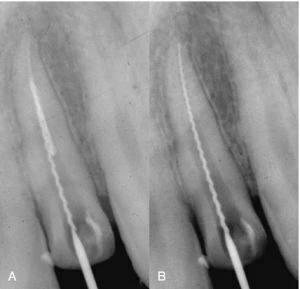

Hình 3. A, Băng qua đầu mũi peeso bằng một trâm H. B, việc điều trị lại được tiến hành sau khi lấy mảnh gãy ra.

Hình 3 minh họa cho việc đi vòng qua và tháo thành công một mảnh đầu mũi peeso tại giữa chân răng của một răng cửa bên hàm trên, sử dụng trâm H.